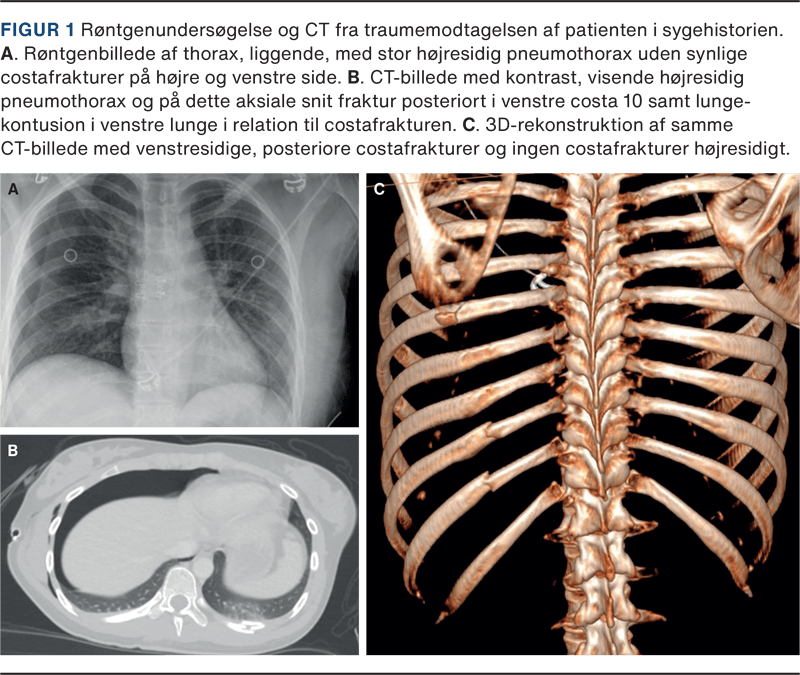

På røntgenundersøgelse af thorax fandtes en stor højresidig pneumothorax (Figur 1 A), hvorfor der blev anlagt højresidigt pleuradræn. Der var ikke tegn på trykpneumothorax. Traume-CT viste frakturer i venstre costae 8-12 (Figur 1 B og C) samt multiple øvrige frakturer i venstre side af kroppen og ustabile bækkenfrakturer med involvering af sacroiliacaleddet og os sacrum. I abdomen fandtes kontusion af venstre nyre og pancreas. Der var ingen skader på milten og ingen hovedskader. Der kunne ikke erkendes costafrakturer på højre side, hvor der sås pneumothorax, og omvendt var der ikke pneumothorax på venstre side, hvor patienten havde mindst fem costafrakturer. Der var ikke pneumomediastinum.

Pleuradrænet blev seponeret 16 timer efter anlæggelse, og på kontrolrøntgenundersøgelse sås stort set fuld regression af pneumothorax. På CT udført dagen efter var der fortsat ingen synlige costafrakturer højresidigt.